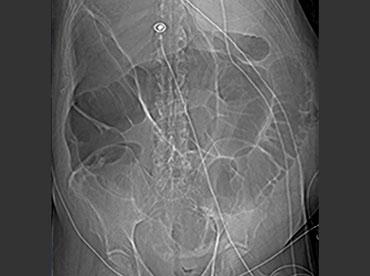

Đây là một bệnh nhân bị tắc ruột non.

Cuộn qua các hình ảnh.

Bạn có thể tìm thấy quai kín và nguyên nhân gây ra nó không?

Khi tiếp nhận bệnh nhân tại phòng cấp cứu với biểu hiện nghi ngờ tắc ruột non (SBO), điều quan trọng nhất chúng ta cần làm, ngoài việc chẩn đoán xác định, là xác định sự hiện diện hay vắng mặt của tình trạng thắt nghẹt.

CT là phương pháp chẩn đoán hình ảnh được lựa chọn trong đánh giá bệnh nhân nghi ngờ tắc ruột non.

Hình ảnh CT của tắc ruột non dạng quai kín phụ thuộc vào hai yếu tố:

- chiều dài đoạn ruột tạo thành quai kín

- hướng của quai ruột so với mặt phẳng tạo ảnh

Nếu quai kín ngắn và nằm trong mặt phẳng tạo ảnh, chúng ta sẽ thấy quai ruột hình chữ U hoặc chữ C.